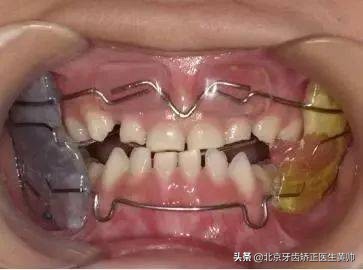

替牙期重度地包天

3、功能矫治器主要用于替牙期或者刚刚换完牙还处于生长发育高峰期的儿童,利用功能矫治器可以矫正骨性错颌畸形。

牙齿矫正